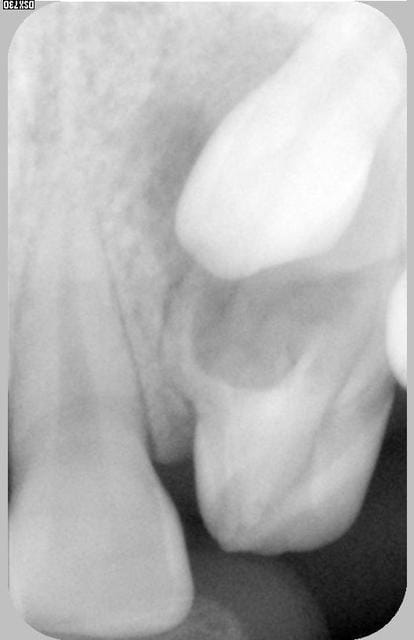

Ouf, super,amg, ta radio est parfaite mais tres mystérieuse: la 2 est une double incisive soudée avec resorption rad? Ou une temporaire bizarroide?

La dent incluse est une canine(13) et celle en évolution ressemble à une latérale def en vestibulaire et à une canine en palatin.

la patiente a 15 ans et se plaint parfois de douleurs sur la 12.

A mon avis, prendre tres rapidement une décision de désinclusion ortho chirurgicale de 13. Je doute que la méga12 fasse un record de longévité dans cette manoeuvre.

Le traitement multiattaches s'impose de fait.

Pas le choix!

Petit facteur apparemment défavorable: le faible diametre MD de cette canine qui al'air quelque peu maigrelette, laissant des diastémes résiduels a fermer sans assymétrie. Mais, bon, c'est de l'ortho.

superposition de 13,53,12?

douleurs sur la 12:cela justifie un examen radiologique plus pousse comme un upper occlusal(plan orthogonal en francais?),un dentscan,une pano pour determiner les rapports dentaires et ecarter un risque de resorption de la laterale